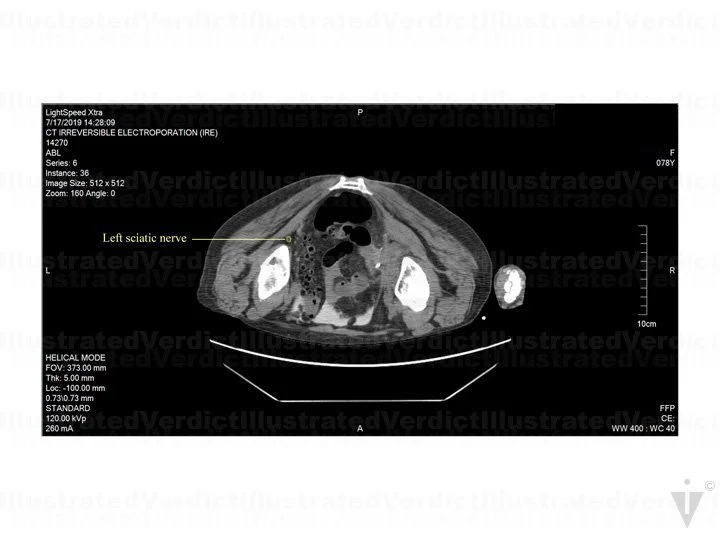

A 78-year-old woman with a history of infiltrating endometriosis presented with persistent, chronic pelvic, back, and flank pain. An MRI revealed a right-sided pelvic endometrioma mass, which encapsulated the right ureter and involved her pelvic nerves. She had a stent placed in the right ureter, and unfortunately, the pain increased. She underwent a CT-guided IRE as treatment. Post treatment, she felt pain in her right foot extending up her calf, and she experienced limited feeling in her right toes, foot, or ankle. A month after the procedure, her right pelvic, back, and flank pain had resolved, but she continued to have right leg paresthesia (pins and needles with numbing sensation). Unfortunately, nerve damage was a risk of the procedure. The jury found in favor of the defense.